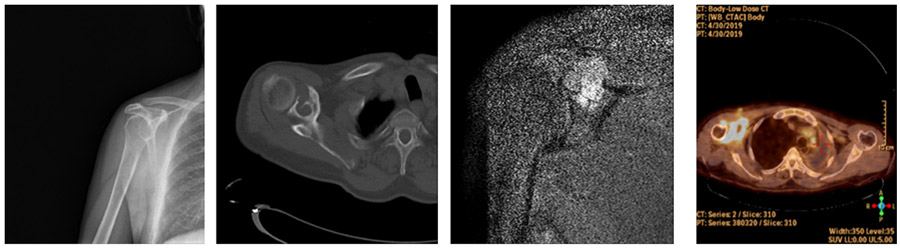

CASE 1: Lung cancer increases the risk of fracture in the right shoulder blade (scapula) due to metastasis.

Before the surgery: While no significant problems are visible on X-ray, CT scans show bone damage, MRI reveals tumor tissue extending beyond the bone, and PET scans show significantly increased tumor activity.